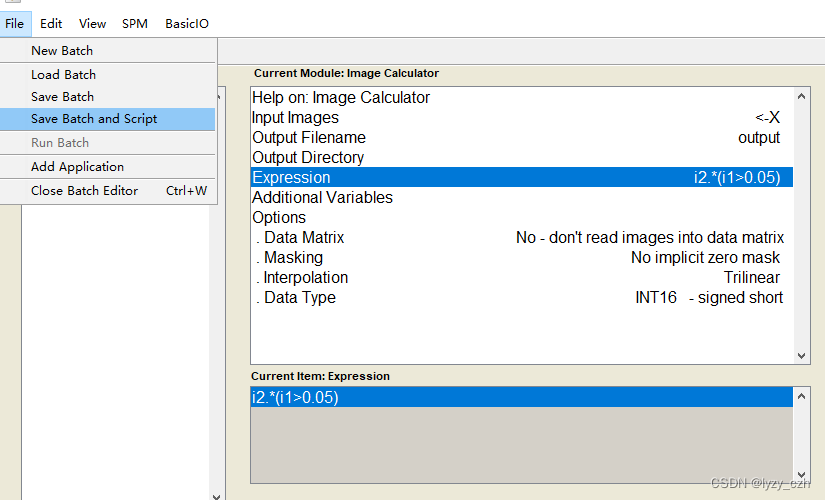

注意在Image Calculator的Expression输入是固定的因此可以直接在这里输入如下:

4、生成batch脚本

选择保存脚本的路径